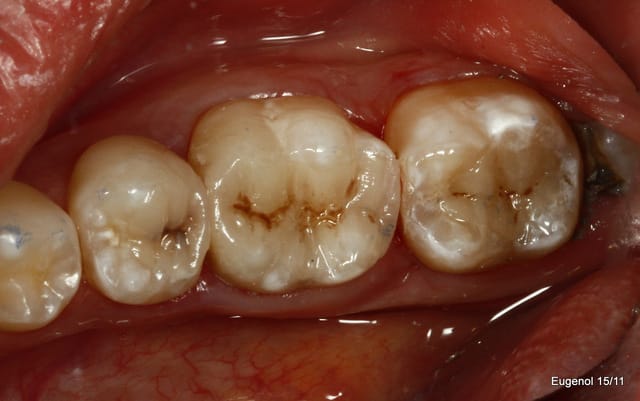

Ben les photos finales c'est après réglage de l'occlusion sinon c'est pas drôle.

Quand on s'appuie sur les cuspides restantes et qu'on donne une morphologie assez naturelle, en général il y a peu de retouche occlusale.

Sinon je fais les sillons secondaire a la sonde.

C'est du compo Enamel HRI en dentine et Esthelite en email qui se sculpte facilement et reste pourtant souple et autolissant...

Le polissage c'est des brossettes chargées en silice, et avec de la pâte à polir.

la radio et la photo a 1 mois